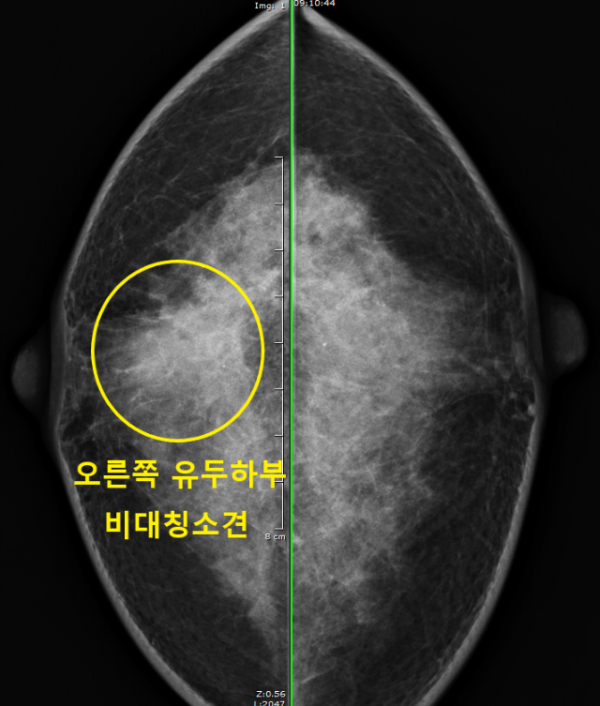

다른병원에서 시행한 유방촬영사진을 먼저 확인해보았습니다.

유방촬영상 치밀유방 소견이었지만 오른쪽 유두아래쪽에 왼쪽과 다른 국소 비대칭 소견이 관찰되었습니다.